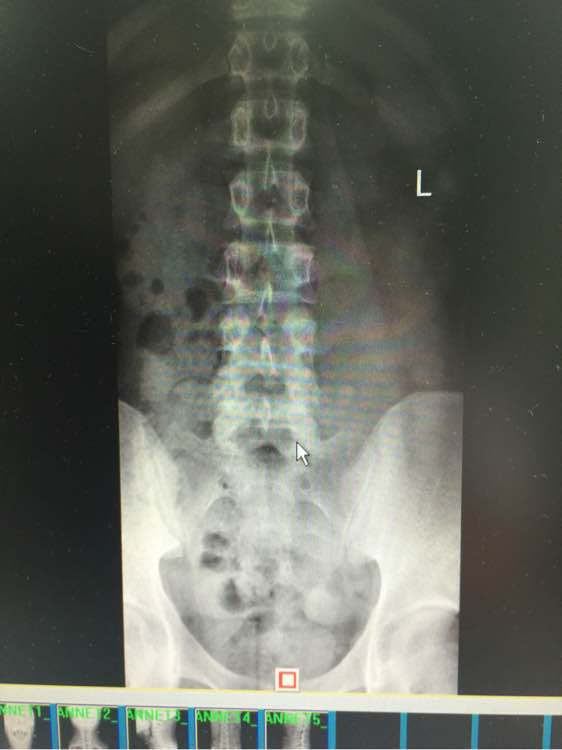

求吧友们帮我看看,寰枢椎关节半脱位,供血不足

站不稳,坐不稳,走不稳, 做什么都飘飘的,走路不平衡,躺着还有塌陷的感觉 除了早上醒来 舒服点,越到下午越来越严重, 感觉无时无刻人就像在船上 左右摇晃的 偶尔更换体位 耳朵鼓鼓的 (这是国庆最严重时候 现在还是晕,没那么晕了,但还是没好 以下一直影响生活到现在)尿尿要扶墙,洗澡不敢洗太久 靠着墙,刷不了牙,刷牙晃动脑袋也更晕,有时候晚上坐着就犯晕,血压高,145 95以上 躺着血压就正常

寰枢椎半脱位引发的眩晕,手法复位1-2次即可

寰枢椎半脱位可以通过牵拉旋转头部使之归位。不难治啊。跟脱臼治法差不多。对了你颈椎上带的东西对你这病作用不大。赶紧找个正骨的复位。。。。。。

确认一下脊髓有没受伤,看图你不严重可以自己修复,就是扶正骨头。

脊髓略受压,没受伤

椎体对血管有压迫。脖子上的那玩意最好不带,时间长了会让寰枢关节变松,脑袋变成拨浪鼓。

被医生吓坏了,不过是第一颈椎左旋了一点,导致一边的入脑的肺动脉憋住,所以大脑缺氧头晕,寰椎和头颅接缝是不动椎,如果脱位你早就瘫了。平躺,头抬起来,迅速常鼻子方向15度旋转复位,听到卡擦就放手,复位后就脑供血正常了。